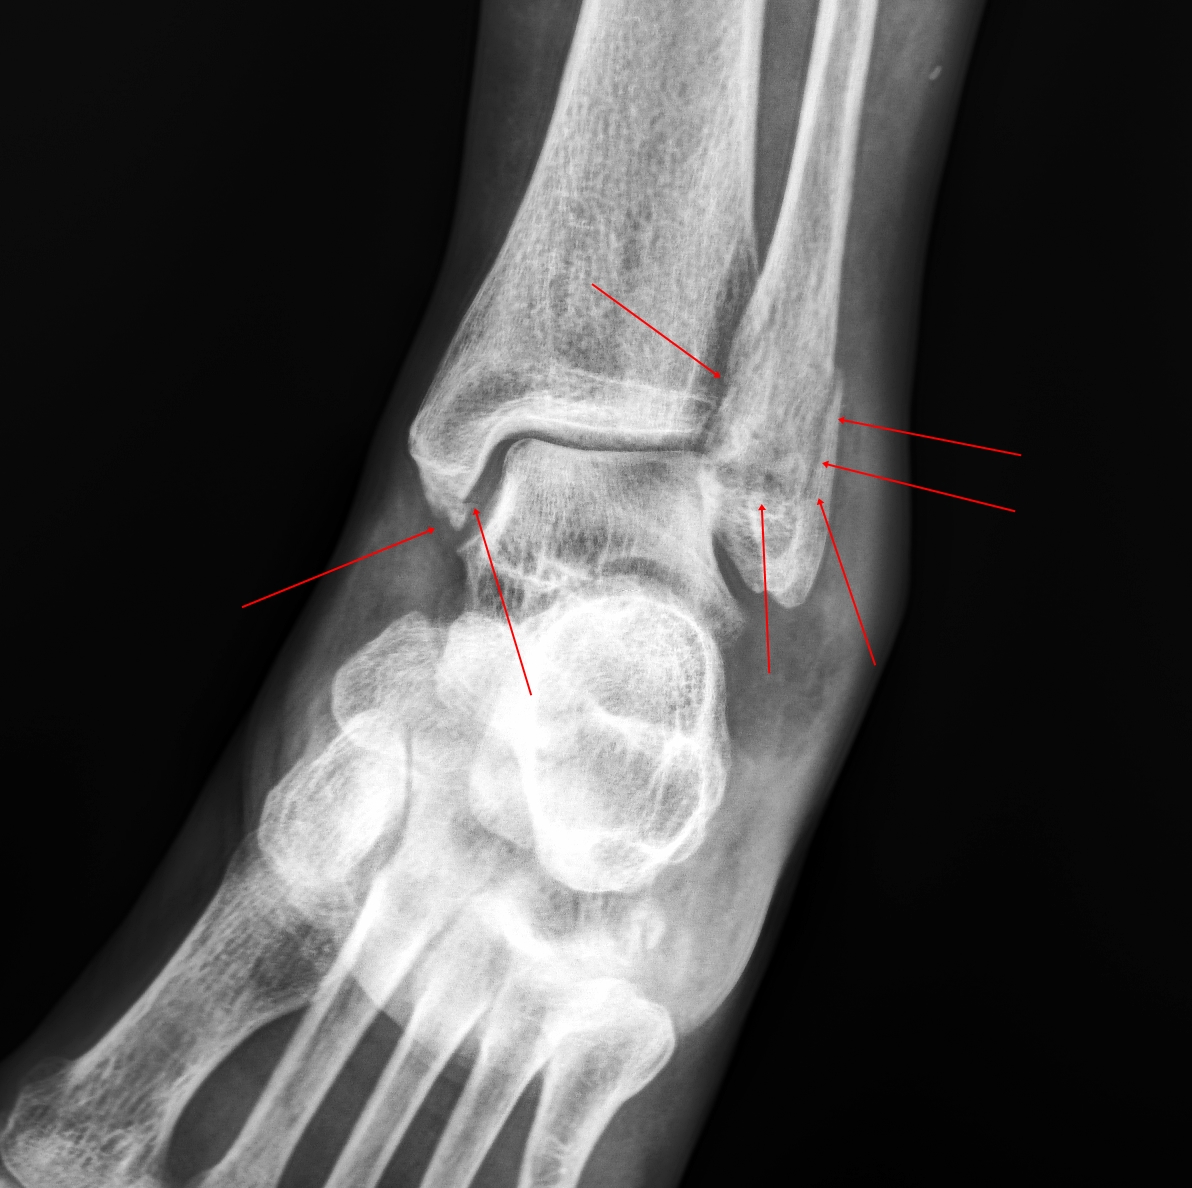

ตรวจร่างกาย ข้อเท้าและเท้าบวม เดินกะเผลก ไม่สามารถยืนลงน้ำหนักขาข้างซ้ายข้างเดียว กดเจ็บด้านในและด้านนอกข้อเท้า แต่หลังเท้ากดไม่เจ็บ ส่งเอกซเรย์ข้อเท้า พบมีกระดูกข้อเท้าซ้ายแตก เลื่อนนิดหน่อย